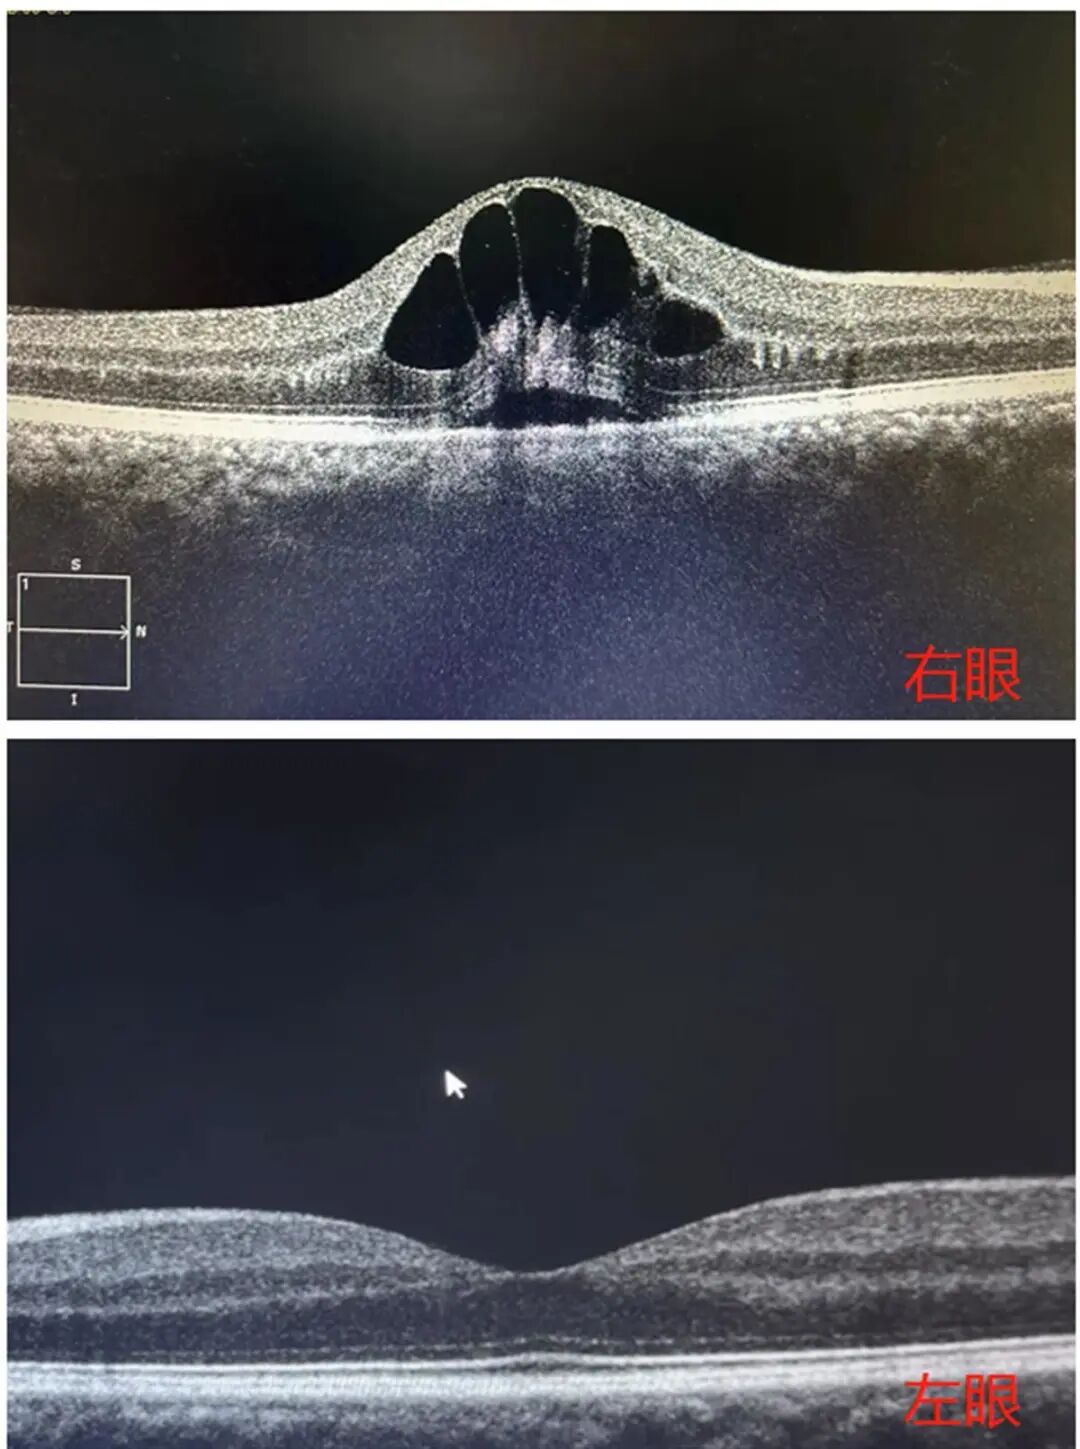

近10天以来,武汉市民刘师长发现本身的视力下降得厉害,到病院搜检发现为视网膜静脉壅塞,眼底黄斑区显现“花瓣”状囊样水肿。

搜检可见,眼底黄斑区显现“花瓣”状囊样水肿

经搜检,刘师长右眼视力仅为0.3。在问诊过程中得知刘师长有高血压病史,但平时并未进行治疗和干涉。于是杨兰马上为其放置了血压搜检,搜检究竟显露刘师长血压高达162/115mmHg(正常血压值为90-140mmHg)。进一步搜检发现,刘师长眼底黄斑区出血及渗透,显现花瓣状囊样水肿,被诊断为“右眼视网膜静脉壅塞”,需要实时进行降血压的治疗后,再完美眼底造影搜检,以便进一步治疗。